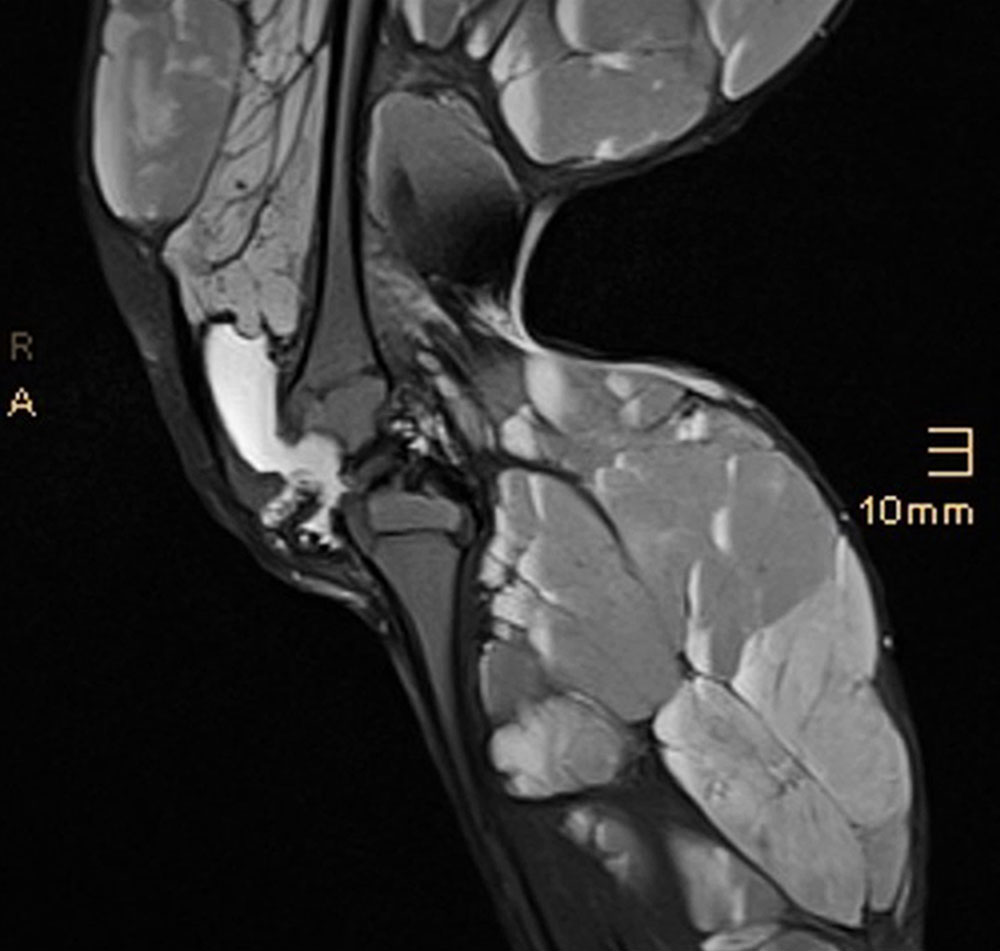

In patients with kaposiform hemangioendothelioma (KHE), tufted angioma (TA) and Kasabach-Merritt phenomenon or extensive venous malformation (VM) with localized intravascular coagulation (LIC), coagulation activation via the vascular anomaly may result in massive consumption of coagulation factors and platelets, leading to clinically manifest bleeding. This high consumption can far exceed the reproduction and replacement of necessary clotting factors and platelets, resulting in disseminated intravascular coagulation (DIC). This particularly manifests itself in subcutaneous local hematomas and bleeding even without adequate trauma. This is exacerbated in severe thrombocytopenia by the formation of petechial hemorrhages on the skin (petechiae) and/or mucous membranes (especially recurrent, severe gastrointestinal bleeding that can hardly be stopped).